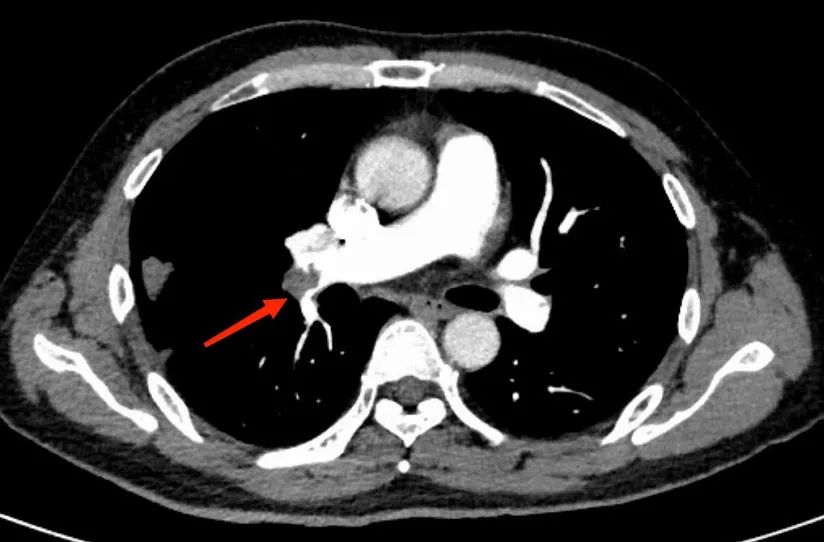

不放过任何一个可疑因素,杨先生在医护人员的陪同下完善了肺动脉CTA检查,检查结果出来,果然是肺栓塞!杨先生肺部那一片片密度增高带有晕征的病变,以及抗感染治疗无效的疑点都得到了解释,是肺栓塞导致了肺梗死。

▲ 肺动脉CTA提示:肺栓塞